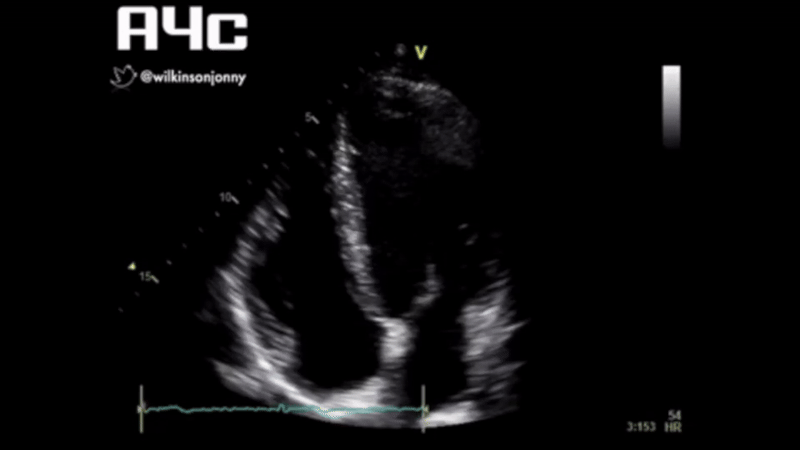

HR

86

CO

4.2

CI

3.12

SVR

12.2